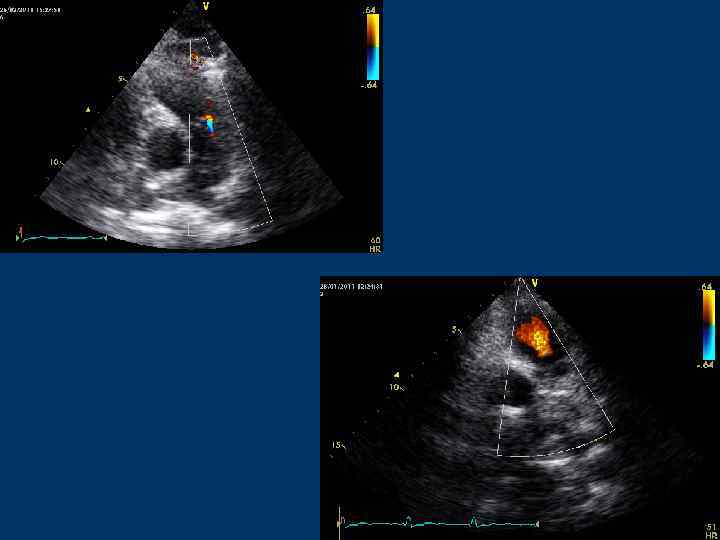

Трансмитральный диастолический поток Позиции: – Парастернальная позиция по длинной оси ЛЖ – Апикальная 4 -камерная – Апикальная 5 -камерная – Апикальная 2 -камерная – Апикальная 3 -камерная – Субксифоидальная

Трансмитральный кровоток

Трансмитральный поток

Трансмитральный диастолический поток Контрольный объем располагают в ЛЖ на уровне концов створок МК или в области фиброзного АВ кольца

Трансмитральный диастолический поток Скорость пика Е – 0, 9 м/с (0, 6 -1, 3) Скорость, пика А – 0, 2 -0, 4 м/с Е/А = 1, 6 -1, 7 (до 2)